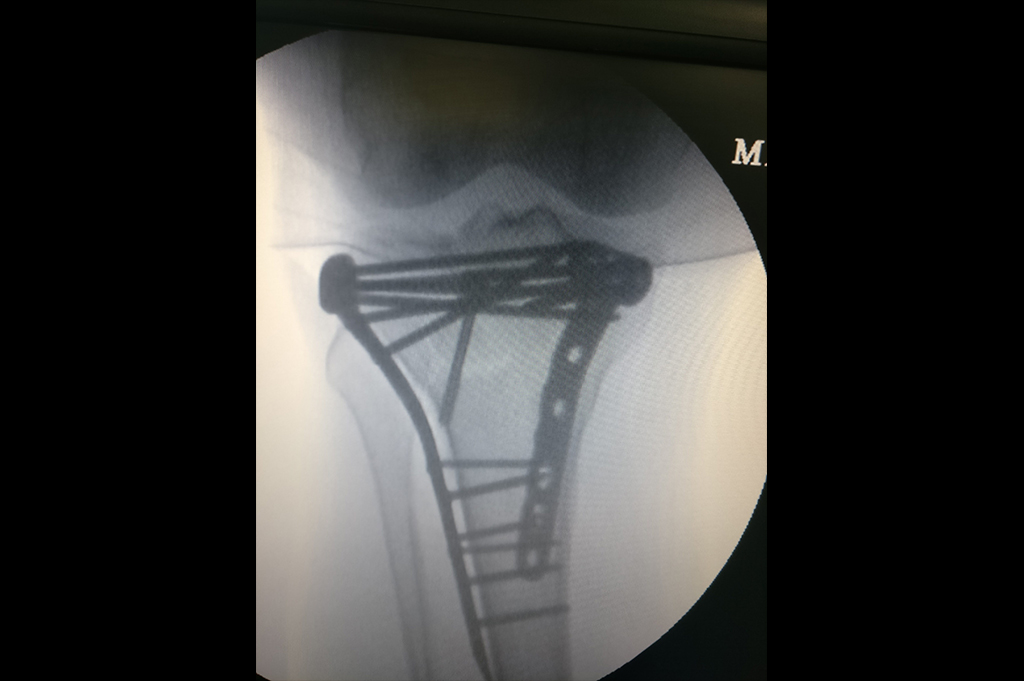

Proximal Tibia